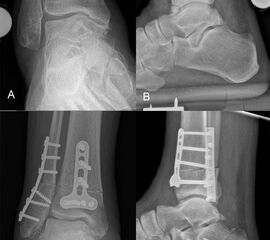

Supramalleoläre Korrektur-Osteotomien

Patienten mit frühen Stadien einer Arthrose am Sprunggelenk sollten auf mögliche bestehende Achsabweichungen hin untersucht werden. Valgus- oder Varus-Deformitäten des Rückfußes und des Unterschenkels zeigen pathologisch veränderte Druckverteilungsmuster insbesondere im OSG, was langfristig zur Entwicklung einer asymmetrischen Sprunggelenks-Arthrose führt 116.

Korrektur-Osteotomien können die normale Biomechanik des OSG wiederherstellen und damit den degenerativen Prozess aufhalten bzw. verlangsamen 117.

Die supramalleoläre Osteotomie ist ein gelenkerhaltendes Verfahren, das der Behandlung des exzentrischen Knorpelverlustes infolge einer übermäßigen Varus- oder Valgusfehlstellung vorbehalten ist. Der Grad der supramalleolären Fehlstellung hat einen signifikanten Einfluss auf die Kraftübertragung auf die Gelenkoberfläche 119. Die daraus resultierende fokale statische und dynamische Überlastung im Gelenk führt zu einer raschen Degeneration der Gelenkoberfläche 116120.

Supramalleolare Osteotomien werden durchgeführt, um die mechanische Achse neu auszurichten und so die Belastung im Sprunggelenk neu zu verteilen, mit dem Ziel, die degenerative Kaskade zu verzögern oder zu stoppen 118121122

Indikationen für eine supramalleoläre Osteotomie sind asymmetrische Valgus- oder Varusarthrosen mit mindestens 50% erhaltener tibiotalarer Gelenkoberfläche. Kontraindikationen sind ältere Patienten mit einer Instabilität des Rückfußes, die durch eine Bandrekonstruktion nicht behoben werden kann, Patienten mit schweren vaskulären oder neurologischen Erkrankungen der betroffenen Extremität, entzündlichen Arthritiden und aktive Infektionen.

Zur Vollansicht und zum Lesen der Bildbeschreibung bitte das Bild anklicken.